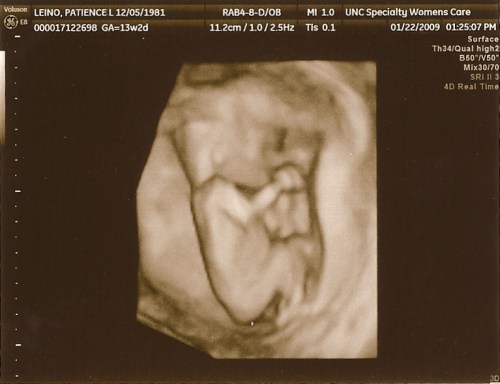

3D Ultrasound 13wks

Today’s appointment went as well as possible.  We met with a genetic counselor to review family history and to understand the range of testing available to us at each stage of the pregnancy.  We were pleasantly surprised to have the same counselor who talked with us during our pregnancy with Isaac.  She remembered our story and was very thorough in updating our history, as well as explaining the options available.

Blood work was drawn on Patience for early screening of syndromes such as Downs and Edwards (Trisomy 18).  Studies have shown correlation between the existence of syndrome/cardiac anomalies and the amount of fluid found at the back of the baby’s neck (nuchal translucency) between 11 and 13 weeks gestation.  Normal range of fluid is 1 to 3 millimeters.  Anything above 3 mm can be indication of a syndrome.  Thankfully, our little one’s fluid measured right at 1 mm!  Our baby’s skull and brain were also examined for early structural anomalies.  We were grateful to hear none could be detected at this time.  Everything measured today looked normal for this stage in the pregnancy.  Praise God for a good report!  We hope to hear back on the bloodwork results sometime next week.

The best part of our visit was certainly the ultrasound.  Our baby was chomping away and waving, but had its face buried against the uterine wall.  Of course, much like Isaac, our little one was refusing to give us a clear shot of its face and decided to fall asleep halfway.  Those Leino kids are stubborn!  Our ultrasound tech did happen to tell us the gender of Baby Leino.  We’ll have it “officially” confirmed at our 18 week ultrasound, but usually this form of i.d. is 95% accurate.

Looks like we’re having a GIRL!